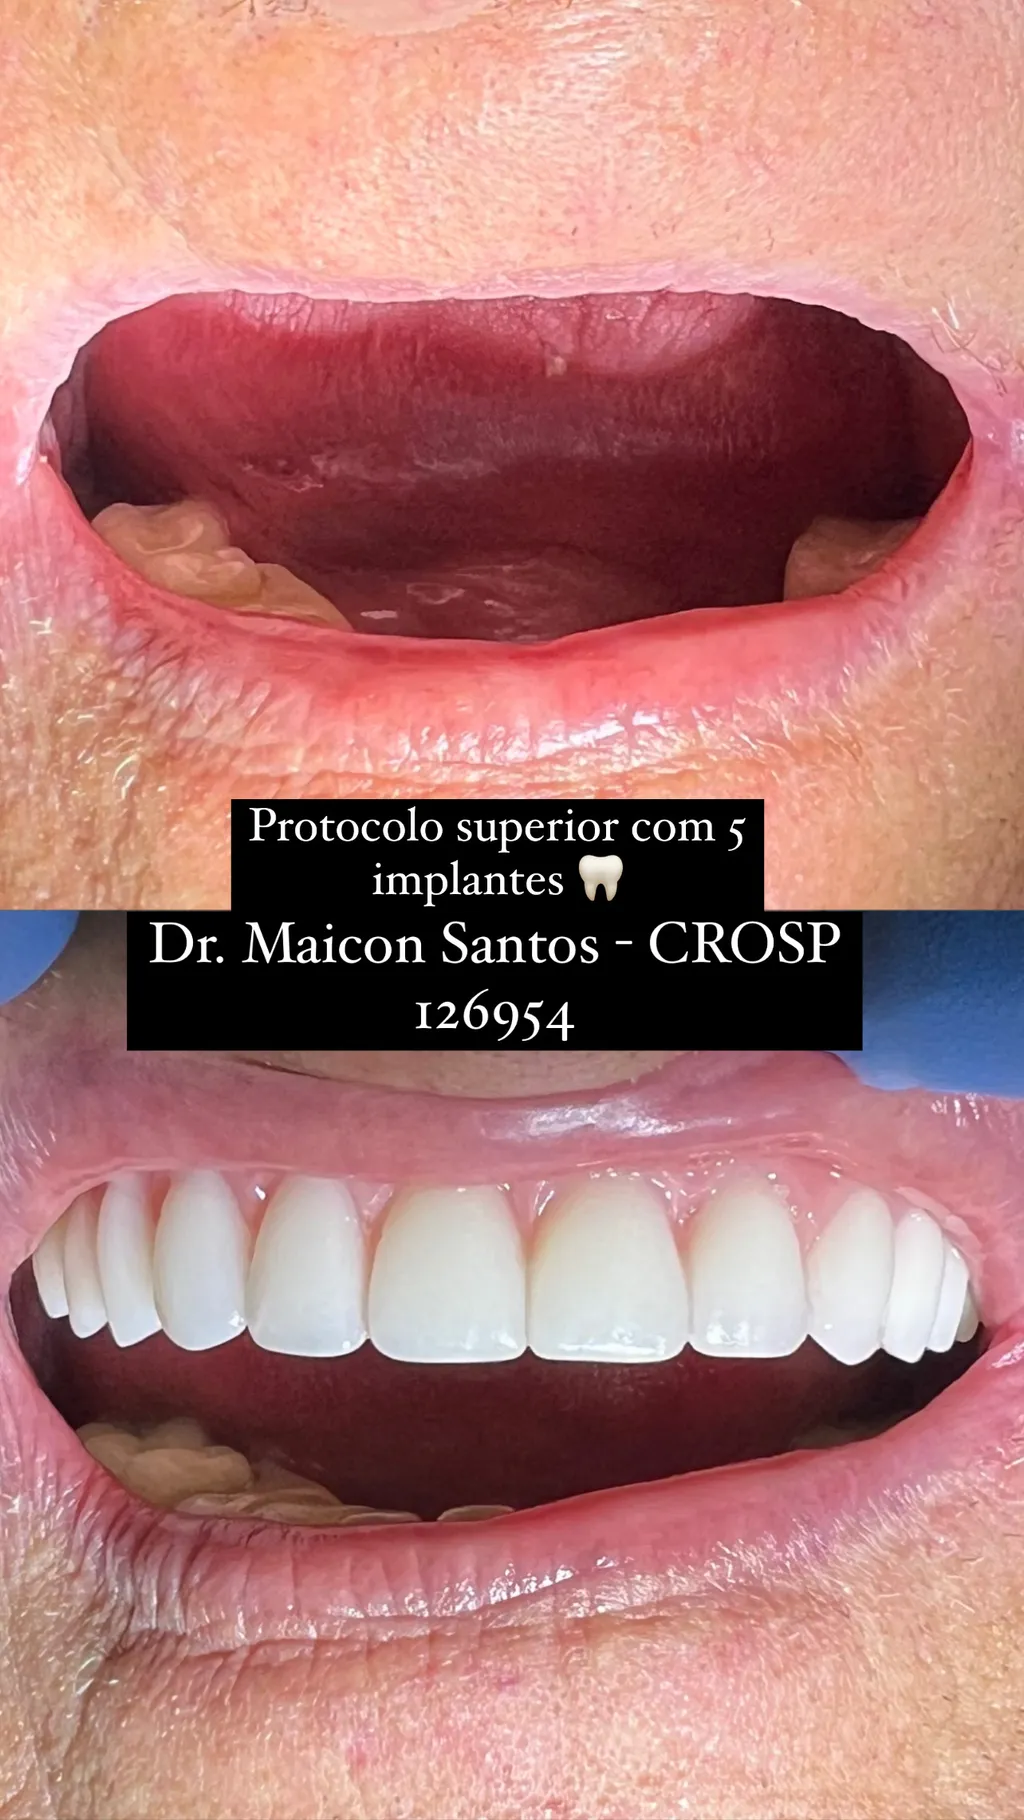

Paciente (Superior)

Protocolo superior com implantes